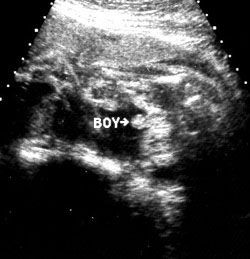

آلت تناسلی پسر بطور واضح در بین پاهای او مشخص در هفته بیست و سوم بارداری می باشد. در هفته بیست و سوم شما 5 ماهه باردار هستید. جنین شما حدود 501 گرم وزن دارد و قدش 28.9 سانتی متر است. او حالا به اندازه یک گریپ فروت است.